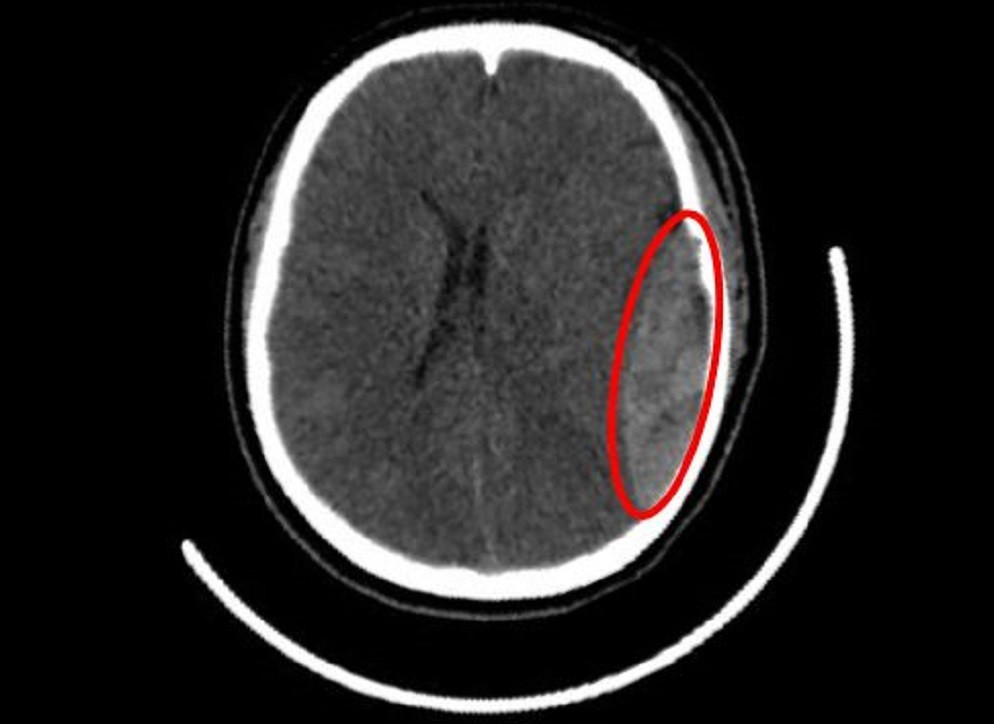

Hình ảnh kiểm tra vị trí chấn thương sọ não của nữ sinh

Hình ảnh CT scan cho thấy rõ vết nứt trên hộp sọ cùng với hiện tượng tụ máu ngoài màng cứng ở khu vực vùng thái dương bên trái. Đây là dạng tổn thương rất nguy hiểm nếu không được can thiệp sớm vì máu tụ có thể tạo áp lực lên não bộ gây giảm chức năng thần kinh hoặc thậm chí tử vong. Bác sĩ chuyên khoa đã đánh giá tình trạng này cần phẫu thuật khẩn cấp để loại bỏ máu tụ và ổn định sức khỏe bệnh nhân.

Máu tụ ngoài màng cứng thường hình thành do rách mạch máu giữa xương sọ và màng não khiến máu lan truyền tạo áp lực lớn lên não bộ bên dưới. Tình trạng này diễn biến nhanh chóng nhưng biểu hiện lâm sàng ban đầu có thể chưa rõ ràng khiến nhiều người chủ quan bỏ qua dẫn đến hậu quả nghiêm trọng như liệt vận động hoặc tử vong nếu không can thiệp sớm.

Cảnh báo nguy hiểm của máu tụ ngoài màng cứng